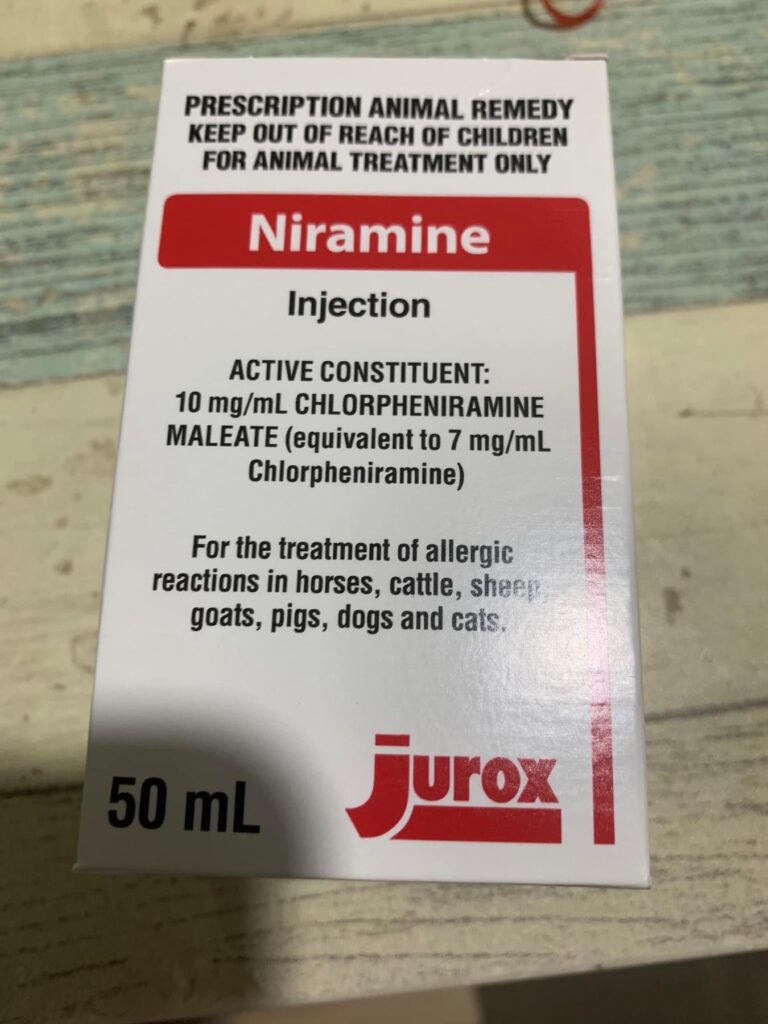

Noon:4.21kg, lose 70g in 3 weeks. Given Subcut, b12 b com jab, ornipural n niramine.

Morning: given Subcut n ornipiral n niramine jab. Did notice he drink water rather frequent, not after niramine

Morning; 4.75 5/10. Today I still didn’t start him on Niramine …

Night: today is his first niramine jab. he is a good boy when he knows I’m jabbing him.

Night: I still give niramine again. And ornipiral. Sayang him

Bought niramine for didi. Dosage stated 0.5ml, daily. Buy online says 1-2mg per cat that’s 0.1-0.2ml only. Side effect: may cause issue for cat w UTI. Tmr I start giving 0.1ml low dose see how.

Morning: bring didi go dr nally review. 4.28kg – lose 60g in 2 days. Cbc taken. HCT up to 30.4%, EOS even higher. Reject doing liver panel. Nothing significant. Just tell me to finish up the 14 days Clav then can stop (till 2.7) Drontal n review every 2-3 months. I’ll decide again Re the allergy jabs.